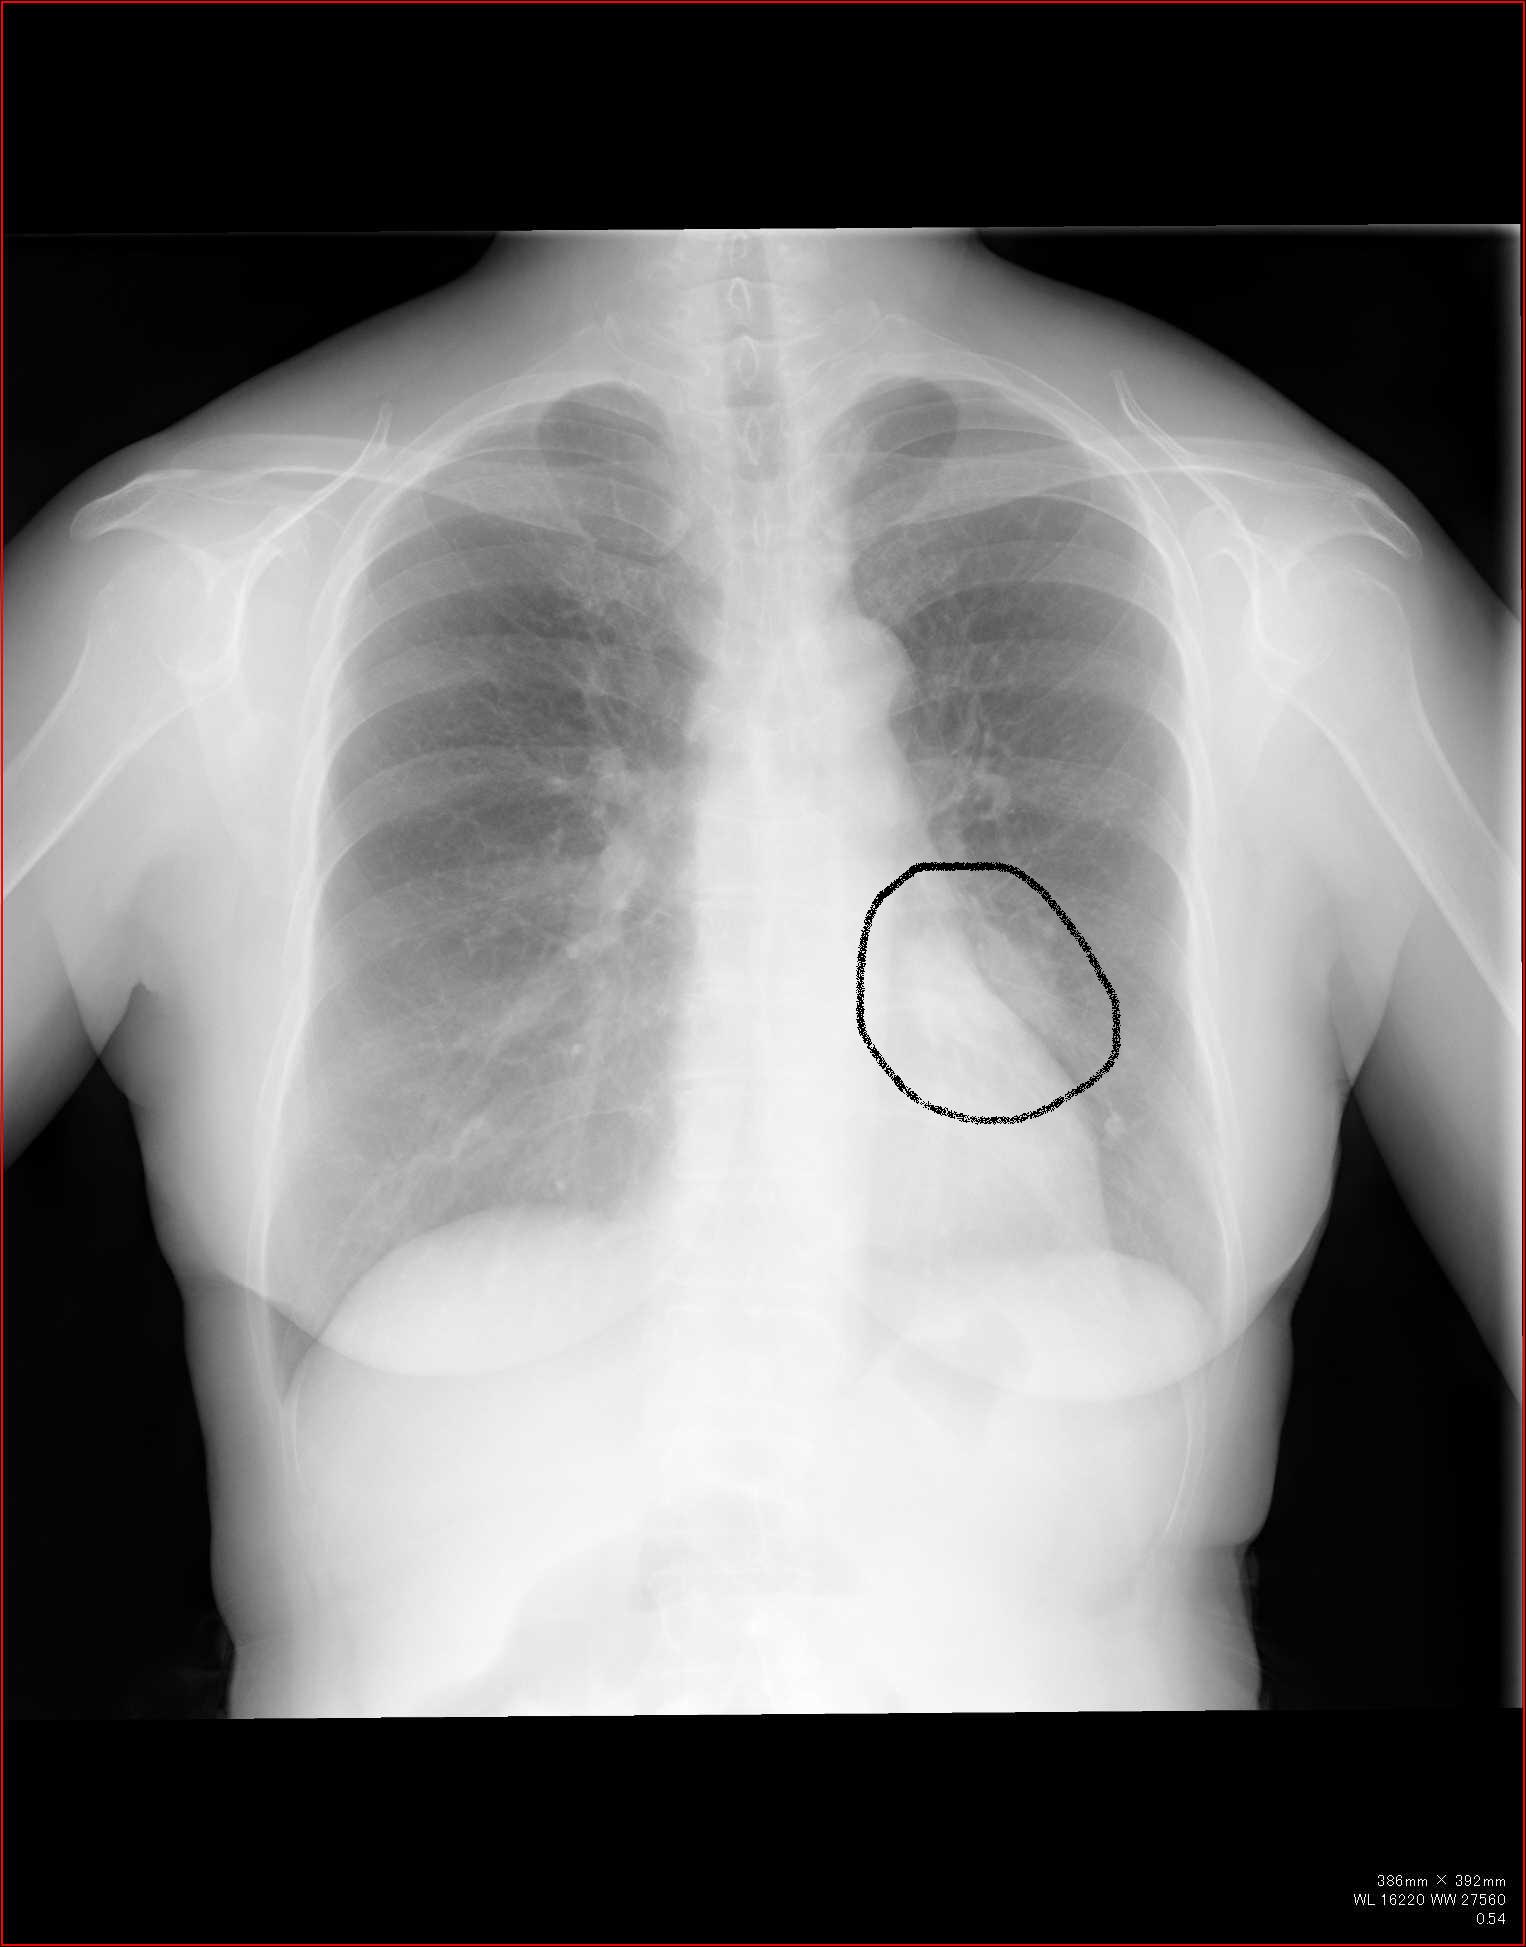

C縦隔や横隔膜の動きを見る

これらの動きから、肺容量の増減がわかります。

縦隔の所見

縦隔を見るときに、ボーッと見ていては所見を見逃します。

各種の線を追いかけていきましょう。